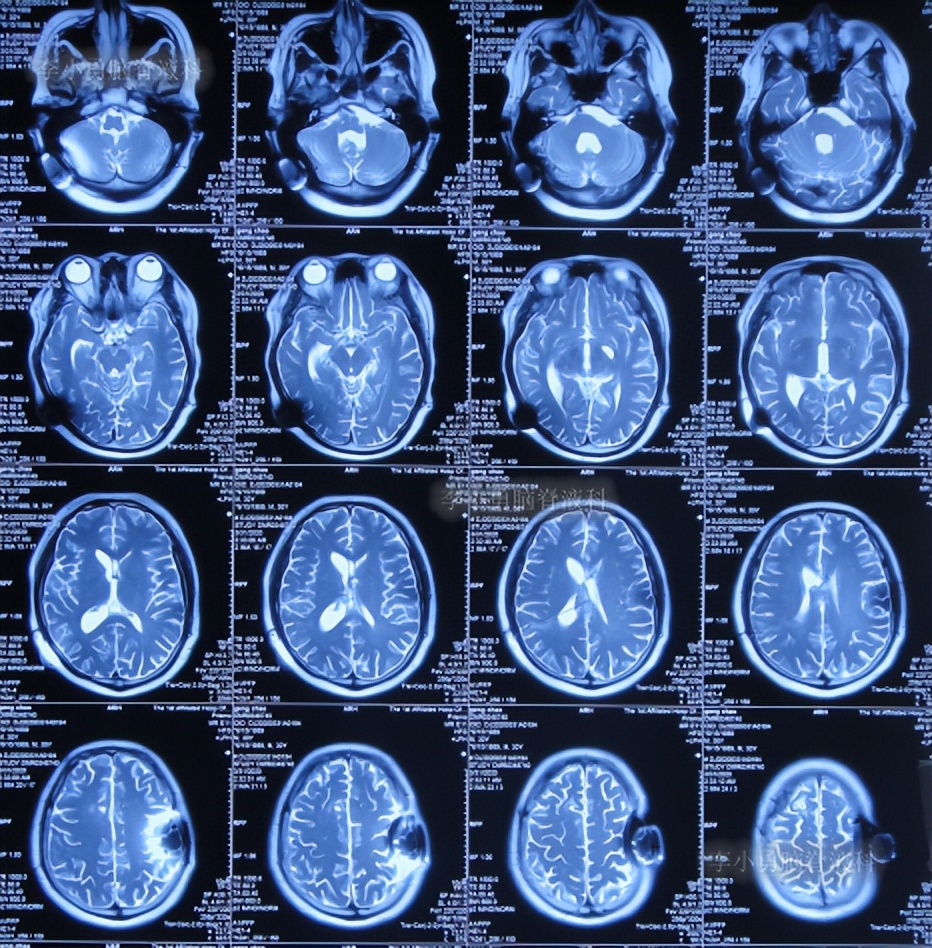

鞍上池脑囊虫性脑积水,三脑室造瘘术无效,2次分流术却均堵管分流重感染致脑室重度粘连,李小勇脑脊液科经3次艰难治疗后获“满意”结果

患者男,34岁,河南省郑州市人。

患者于2018年1月初出现头痛,就诊河南省某中医院,查脑核磁检查示鞍区可疑囊性病变脑积水并间质水肿,左侧前联合异常信号,考虑神经上皮囊肿(片子丢失)。

3天后2018年1月9日,转至上级的河南郑州某三甲医院,诊断颅内占位,脑积水(片子丢失);入院后10天即2018年1月19日,进行了“鞍上池脑囊虫切除术+三脑室造瘘术”。术后病检提示猪囊虫病,给予预防感染、脱水、抗虫等对症支持治疗;住院1月零9天即2018年2月13日,症状缓解后出院。

但出院后17天即2018年3月2日,出现头痛,3天后2018年3月5日(出院后20天),第2次就诊给予手术的医院,诊断脑积水,入院后第2天即2018年3月7日,进行了右侧脑室腹腔分流术,住院半月出院,但出院时虽头痛缓解,但偶有视物重影的症状。

出院后1年半期间,仍时有视物重影的症状,并未给予处理,但到2019年9月27日(脑室腹腔分流术后1年零6个半月),出现头晕,恶心呕吐,视物重影加重,5天后因症状无缓解,就诊于当地的河南省临颍县某医院,查脑CT示脑积水(图-1);给予腰穿检查示颅内压力高220mmH2O。

图-1:2019年10月3日头颅CT